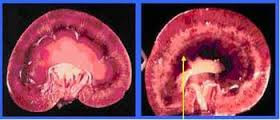

Sỏi

niệu quản nếu không được điều trị kịp thời có thể dẫn đến suy thận

Trường hợp xấu sỏi bị kẹt trong cuống đài thận làm tắc cuống đài thận, dần dần

khiến thận dãn như 1 túi nước, đau quặn thắt.

chúng bị viêm, phù nề. Nhiễm trùng có thể dẫn đến suy thận, hoại tử đường tiểu,

vỡ thận, vỡ bàng quang.